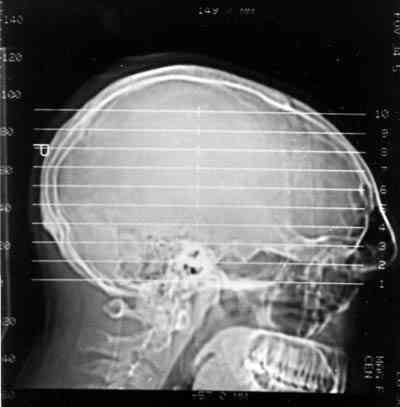

Figura 5

RMN CEREBRAL SAGITAL MOSTRANDO EL SENO FRONTAL HIPERNEUMATIZADO, HACE 10 AŅOS.